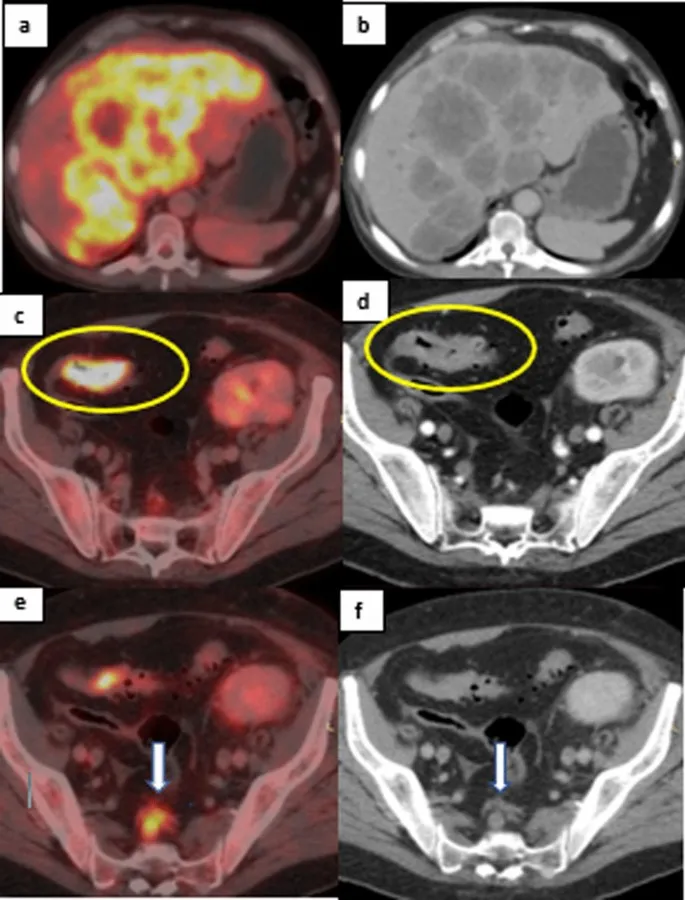

⭐ In modern practice, FDG-PET/CT is a key investigation, often used earlier, to localize metabolic activity and guide targeted biopsies, significantly improving diagnostic yield.